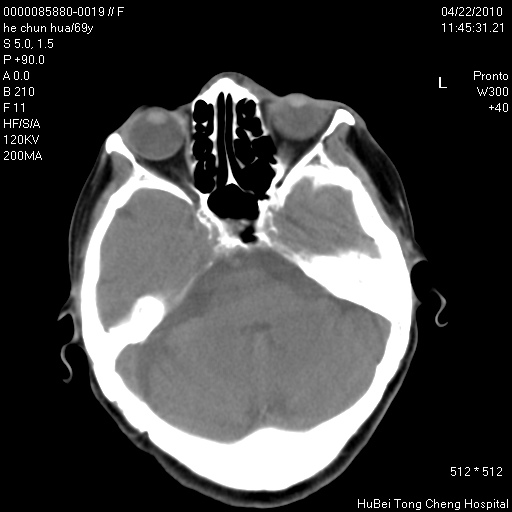

标题: CT25937:女,69Y

硬腭部包块十余年,渐进性增大。